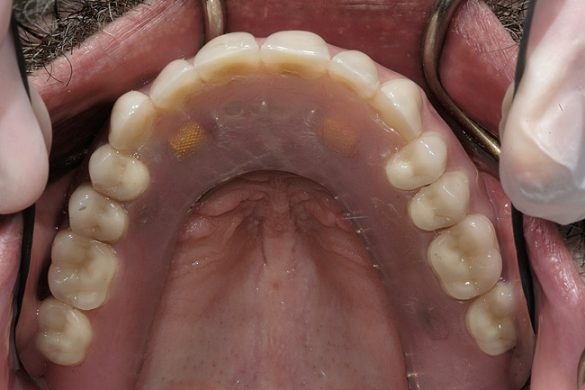

În plus, obiectivele tratamentului au vizat două cerinţe specifice din partea pacientului: rezultatul restaurator să fie suficient de stabil pentru a menţine un dispozitiv de reglare folosit la scufundări, iar palatul expus să facă parte din tratament cu scopul de a preveni alterarea gustului.9-13

Proteza provizorie s-a apropiat extrem de mult de atingerea obiectivelor de ridicare a planului ocluzal pentru estetică şi repoziţionarea palatinală a incisivilor superiori (fig. 7). Încercarea de a eleva planul ocluzal a condus din punct de vedere estetic la situaţia în care planul ocluzal al protezei provizorii era superior faţă de acrilatul care acoperea tuberozitatea maxilară (fig. 8). În cursul perioadei de integrare, proteza provizorie a fost menţinută pe implanturile în curs de vindecare.

Pe perioada integrării implantelor s-au confecţionat proteze noi. S-a amprentat nivelul elementelor fixe prin utilizarea unei tehnici cu lingura deschisă. Înainte de proba machetei, proteza provizorie a fost modificată pentru a închide diastema, permiţând pacientului şi familiei acestuia să decidă dacă doresc menţinerea diastemei în proteza finală. Pacientul a optat pentru închiderea diastemei în proteza finală. S-a stabilit planul ocluzal final, plasat uşor mai inferior faţă de planul ocluzal al protezei temporare.

Matricele siliconice s-au utilizat pentru a concepe locaţia barei şi a ataşamentului pe modelul master cu scopul de a crea grosimea adecvată a scheletului şi a acrilatului protezei. La arcada mandibulară, forma includea o bară cadru întreruptă pe linia mediană pentru a reduce efectul flexurii mandibulare.14-17 Datorită severităţii bolii parodontale, s-a anticipat şi s-a instalat un mare grad de contracţie tisulară. Exista un spaţiu interocluzal adecvat pentru a crea ansamblul barei şi s-au selectat ataşamentele, cu menţinerea înălţimii la un nivel minim. Spaţiul disponibil pentru aplicarea barei se poate vedea cu uşurinţă cu ajutorul şablonului siliconic poziţionat pe modelul master, iar laboratorul a confecţionat bara cu ataşamente. Arcada inferioară prezenta un spaţiu cu 3mm mai mare decât arcada superioară, ca rezultat al ridicării planului ocluzal şi al modificării dimensiunii verticale de ocluzie. S-au folosit cleme pentru a oferi stabilizarea tripodică şi posibila retenţie alternativă în cazul în care elementele fixe pe implante s-ar compromite în viitor. S-a efectuat proba barei şi a ataşamentelor, s-a verificat pasivitatea şi s-au probat machetele din ceară ale protezelor, pe ansamblul de bară şi ataşament, pentru a confirma obţinerea obiectivelor estetice şi funcţionale.